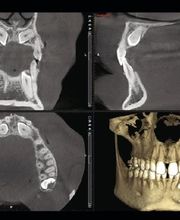

Lo Studio Dentistico del dottor Antonio Grimaldi opera in Sondrio da trenta anni. In un ambiente completamente ampliato e rinnovato, offre terapie chirurgiche, protesico-implantare ( riabilitazioni implantari immediate in giornata), parodontale e conservative di ultima generazione, oltre a tutta la parte dedicata alla prevenzione e all'igiene del cavo orale. L'esperienza di tanti anni di lavoro unita alla digitalizzazione dei percorsi diagnostici ( TAC digitale) e terapeutici ( telecamera per le impronte) proietta lo studio verso le nuove sfide del futuro. Lo Studio esegue anche prevenzione e cure dei denti dei pazienti più piccoli offrendo loro la possibilità di correggere eventuali alterazioni della masticazione. Con il metodo Serenità in Poltrona infine diamo la possibilità a tutti i pazienti che lo desiderano, di essere addormentati (sedazione cosciente) per non vivere alcun stato di ansia durante le sedute operatorie.